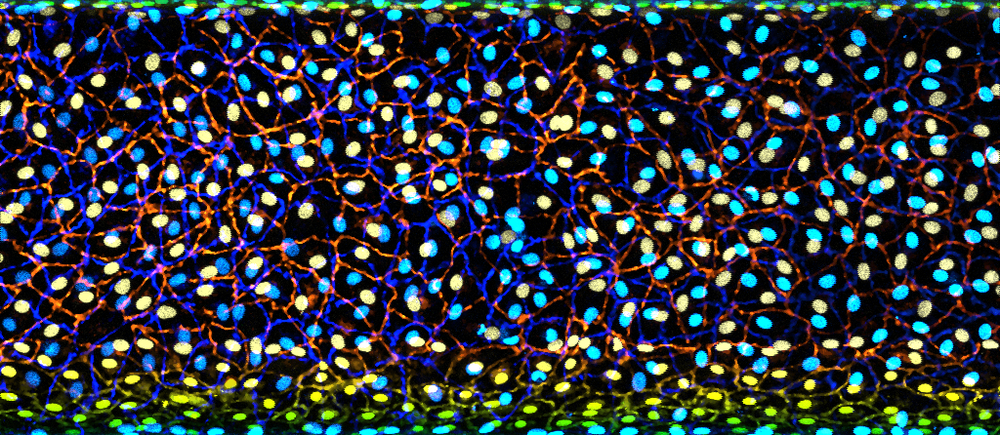

Fluorescent microscopic image showing a dense layer of brightly coloured cells, with blue and yellow nuclei surrounded by an intricate network of red and green cell borders

Growing tiny tubes – entered by Dr Charlotte O’Riordan, Research Fellow This glowing image shows a lymphatic vessel grown in the lab. Hidden within childhood kidney cancers, these vessels can be used by cancer cells to spread. By recreating them outside the body, researchers can study how cancer hijacks these pathways and begin testing treatments to block this process and improve outcomes for children.